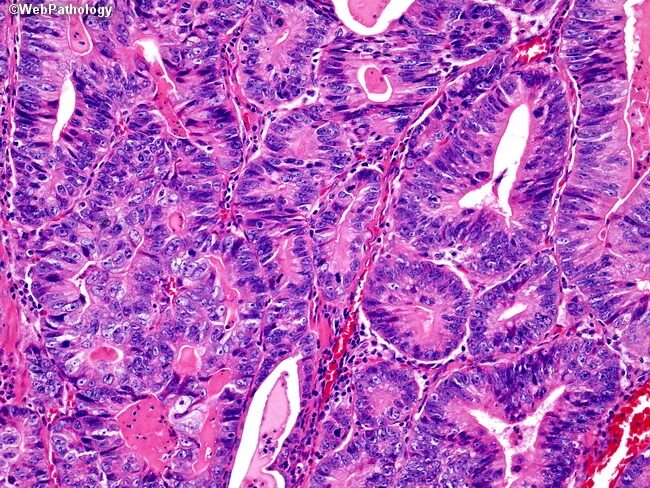

Метастазы в желчном